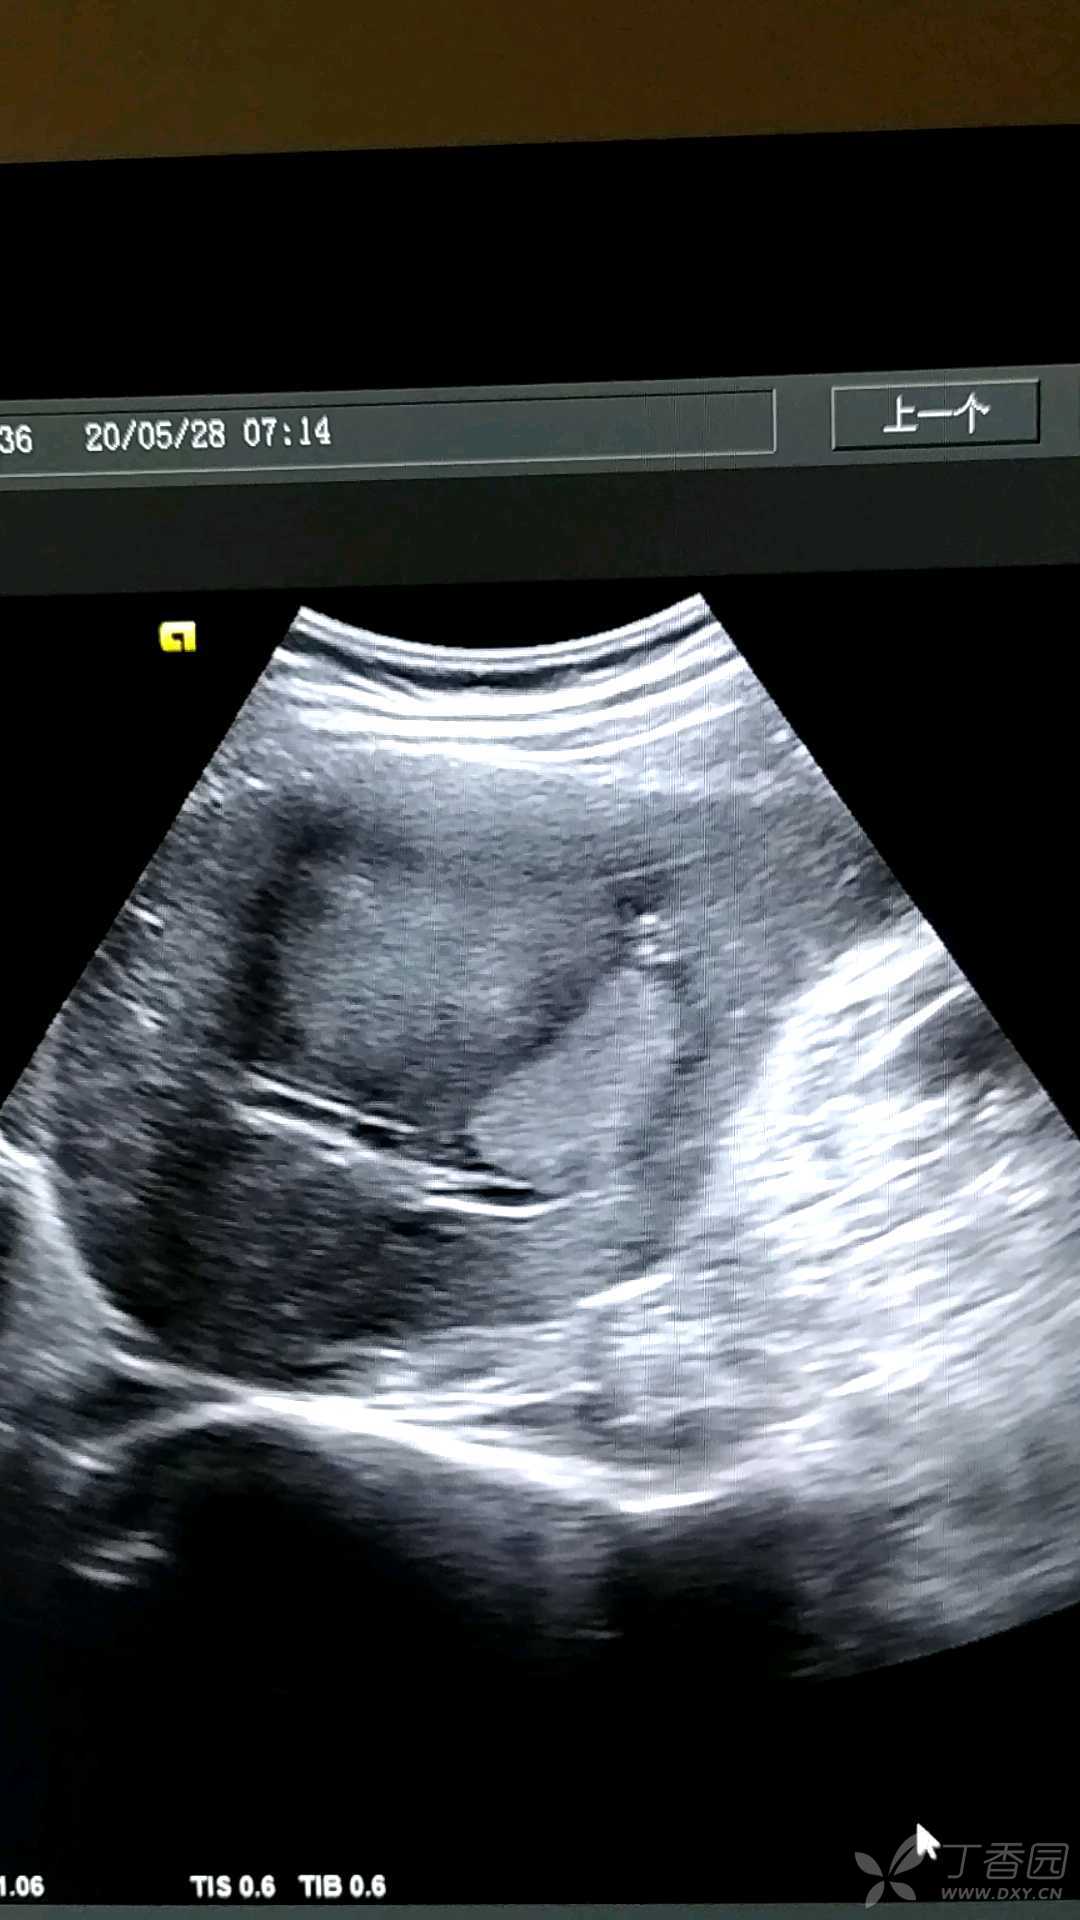

肝癌,男,78岁

图片尺寸720x576